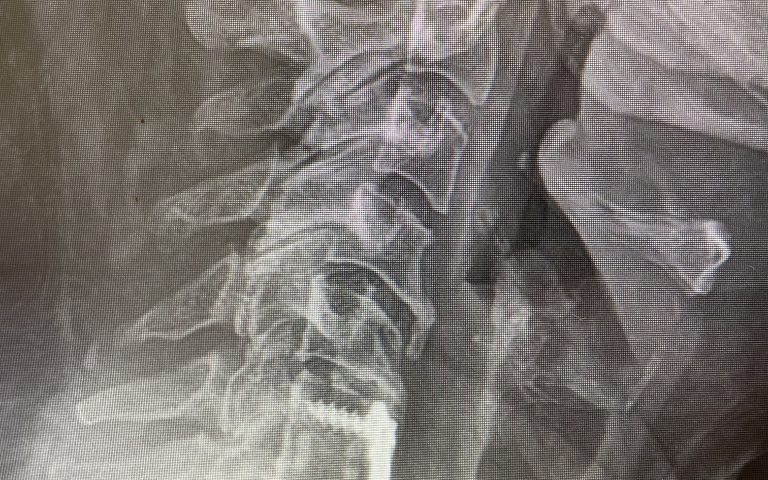

Figure 1: Sagittal x-ray after C6-7 anterior cervical discectomy showing collapse of the C5-6 disc space with fully connected anterior bridging osteophyte and C4-5 partially bridged anterior osteophyte with anterior angulation of C4 vertebral body. Sagittal T2-weighted MRI showing listhesis of C4 on C5 with C4-5 disc protrusion causing cord compression.

On the initial visit she was completely neurologically intact. We recommended physical therapy and ordered cervical x-rays and MRI (Fig 1). It appeared on her x-rays that she had a stable C6-7 fusion segment, but she also had a very collapsed C5-6-disc space. In front of that C5-6 disc space there is an obvious anterior osteophyte bridging the space, in essence autofusing that segment. Right above that at the C4-5 space there was an anterior bridging osteophyte as well with some C4 anterior angulation and listhesis with respect to C5, although the bridging bone did not completely bridge across to C5. Since C6-C7 and C5-6 were essentially non functional, there was biomechanical stress on the next segment, C4-5, which resulted in premature degeneration and instability. This also on MRI caused more stress on the C4-5 disc segment and secondary protrusion with anterior cord distortion. Given this was only a static picture of her spine, imagine how her cord is affected on flexion and extension movements.